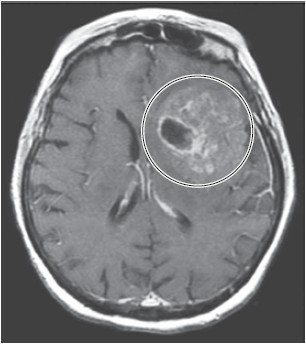

A imagem de ressonância magnética de encéfalo a seguir demonstra uma lesão cerebral captante de contraste em T1. Assinale a alternativa que corretamente identifica a mutação genética mais comum neste tipo de lesão.

(Arquivo pessoal; imagem usada com autorização)